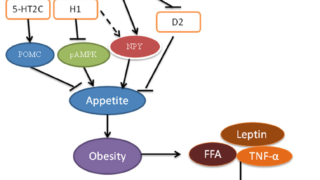

胸腺腫瘍細胞において本来存在していないPIT-1(GH,TSH,PRLの産生に必要な転写因子)が異所性に発現することで免疫寛容破綻が生じ、PIT-1を特異的に攻撃する細胞障害性T細胞が産生され、下垂体GH,TSH,PRL産生細胞を特異的に障害すると考えられている。PIT-1に対する自己抗体が認められる。

TPIT(Corticotroph)、SF1(Gonadotroph)、PIT-1(Somatotroph、Lactotroph、Thyrotroph)。